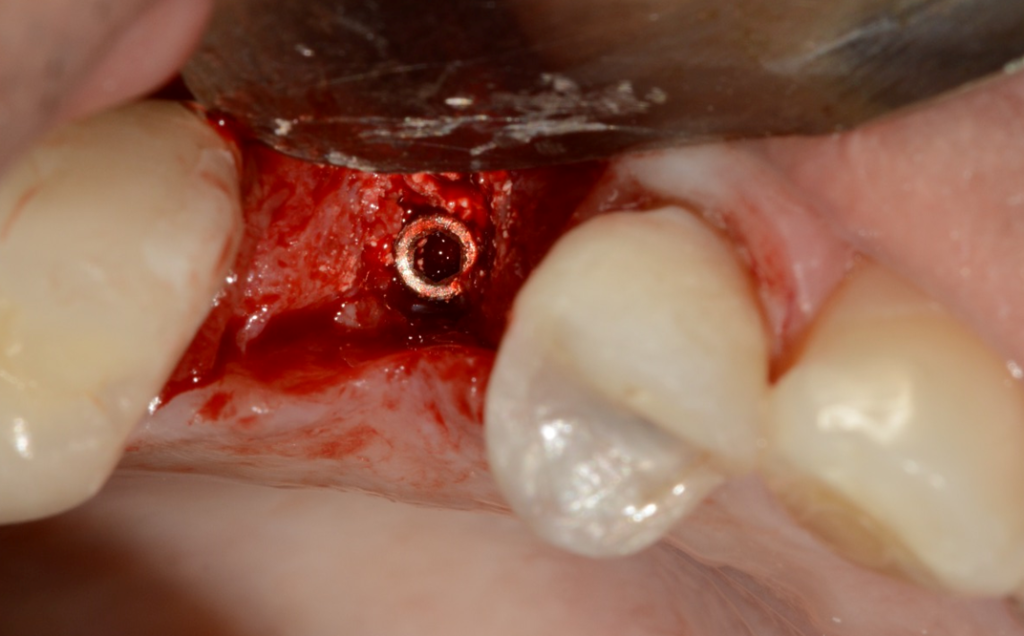

No presente caso, o paciente procurou nossa clínica acreditando que a coroa sobre implante do 15 estava apenas frouxa, e que seria possível resolver apertando o parafuso. Ao exame clínico, apresentava uma coroa cimentada sobre componente UCLA fundida e parafusada diretamente sobre o hexágono do implante (um HE de 3.5 mm de diâmetro e plataforma da mesma medida). Após o corte da coroa para acessar o parafuso, na remoção do conjunto, a plataforma do implante veio anexada à coroa, denotando a fratura do implante, que foi comprovada com radiografia periapical (Figuras 1 e 2). Decidimos por fazer uma prótese adesiva provisória (Figuras 3 e 4) e planejar a remoção do implante com colocação imediata de novo implante, após observado na tomografia cone beam que haveria osso suficiente para isso (Figura 5). O implante foi removido (Figuras 6 e 7) com o uso de broca trefina e fórceps, e um implante Implacil De Bortoli CM Due Cone foi instalado no mesmo momento (Figura 8), com regeneração óssea guiada (ROG) na parede vestibular (Figura 9), que havia ficado muito fina (enxerto ósseo particulado + membrana de colágeno). Apesar de termos obtido bom travamento do implante (45 Ncm), optamos por deixá-lo sem carga pelo período de cinco meses, para respeitar o tempo da ROG (Figuras 10 e 11).